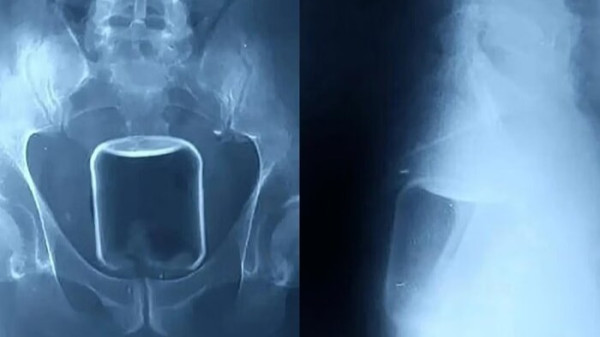

Copo de metal

Homem precisou usar bolsa de colostomia por três meses, após inserir um copo de metal no ânus e precisar passar por cirurgia de remoção, que resultou no corte de um pedaço do intestino. O objeto de 14 centímetros de comprimento e 7 de diâmetro foi introduzido pelo homem após uma bebedeira.